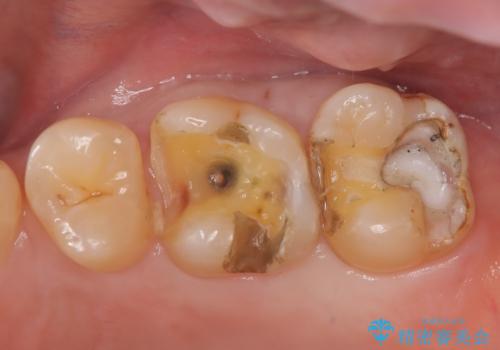

- 定期検診にて虫歯を認めた患者さんです。

患者さんの希望により、修復物の割れる心配が少ないゴールドインレーでの治療を行いました。